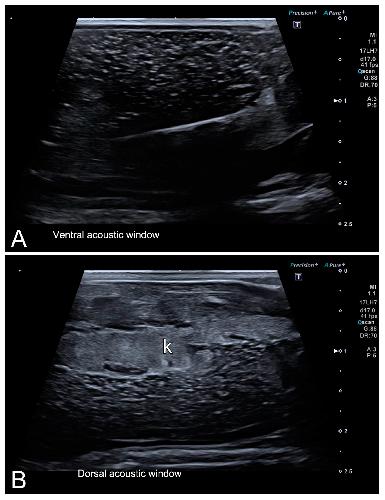

Sex Determination in Two Species of Anuran Amphibians by Magnetic Resonance Imaging and Ultrasound Techniques., Ruiz-Fernández MJ, Jiménez S, Fernández-Valle E, García-Real MI, Castejón D, Moreno N, Ardiaca M, Montesinos A, Ariza S, González-Soriano J., Animals (Basel). November 18, 2020; 10 (11):